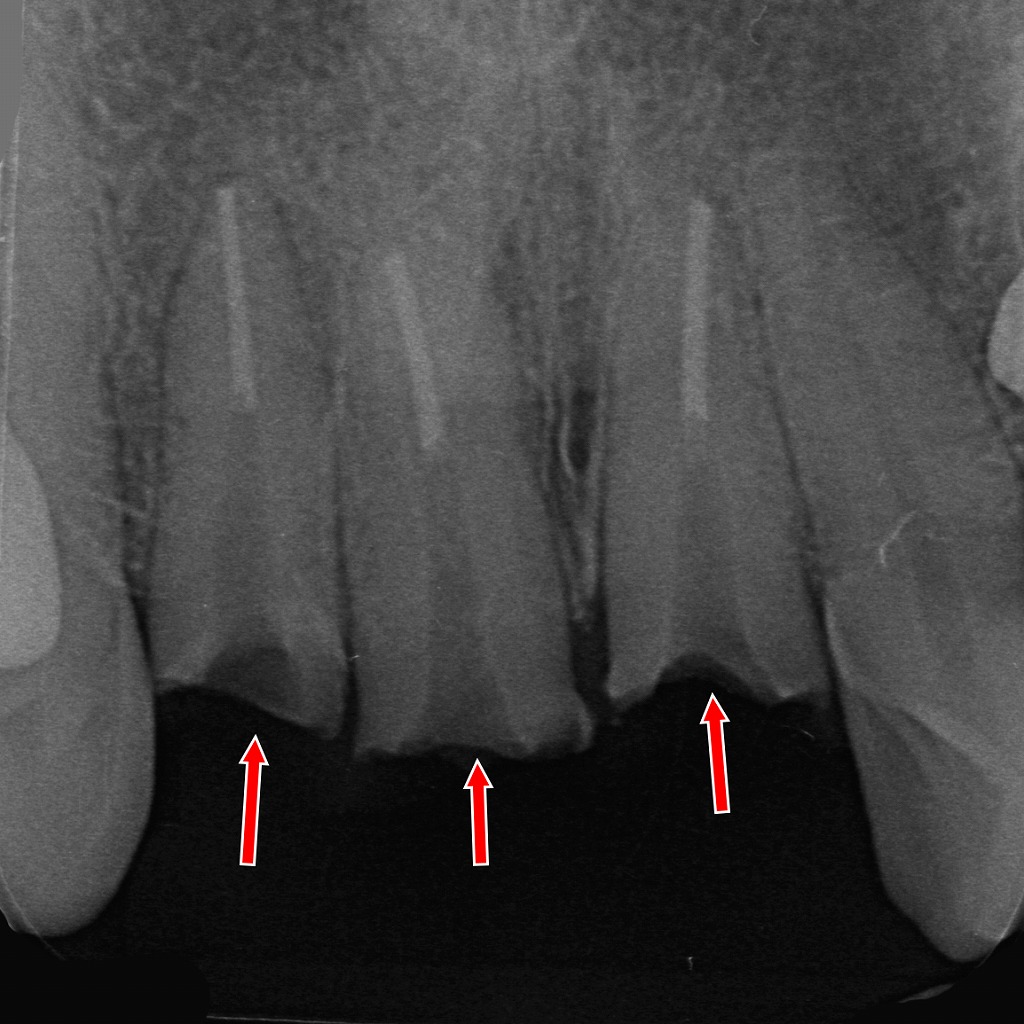

■ 画像の解説

このX線画像は、前歯3本の折れたクラウンとメタルコアをすべて除去した後の状態を示しています。

赤い矢印の部位では、クラウンとコアを撤去したことで歯根の形態がそのまま露出しているのが確認できます。

主なポイント:

- 3本とも根管治療済みで、根管内のガッタパーチャが確認できる状態

- 破折していたコアを除去したため、歯冠部はほぼ失われ、歯根のみが残存

- 根尖側に大きな透過像はなく、破折は歯根の歯頸部付近で生じていました

クラウンとコアを外すことで、破折線・歯根の状態を直接評価できる段階です。